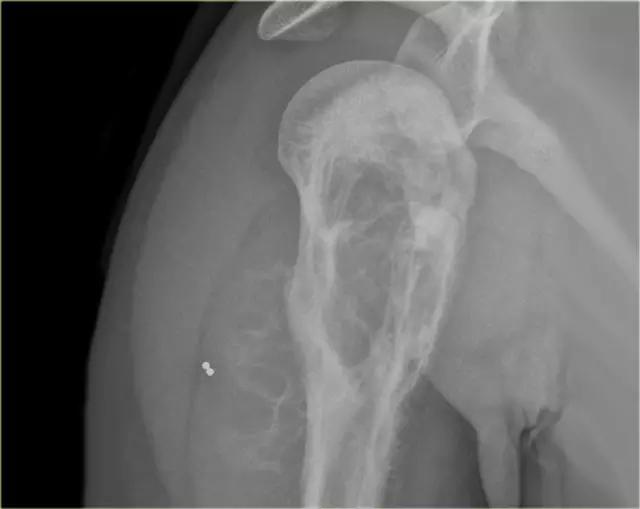

混合溶骨和硬化病变在近端肱骨与不规则的骨皮质破坏。存在侵袭性骨膜反应和软组织块。